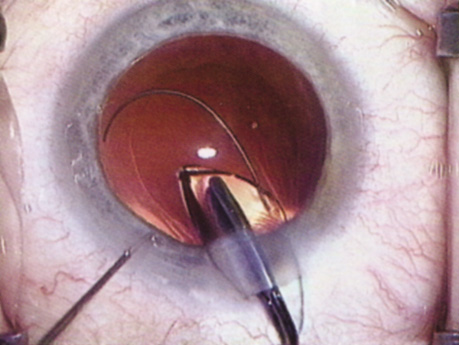

A mature cataract precludes visualization of the fundus. A B-scan ultrasonographic examination provides a real-time, two-dimensional (2D), cross-sectional image of the globe along the marked axis of the probe (Fig. 3). Cataracts are more common in patients with chronic retinal detachment, prior trauma, or intraocular tumors; therefore, a B-scan study is helpful in excluding structural posterior segment pathology before surgery on a mature cataract. Although a negative result to B-scan evaluation is reassuring, the surgeon should remember that it does not predict postoperative visual outcome. The B-scan can be thought of as a picture of Cincinnati from an airplane; the office buildings may all be standing, but you cannot tell whether the people in them are working.

Fig. 3. This B-scan ultrasound shows a normal looking posterior pole, without retinal detachment or intraocular mass. The vitreous cavity is echo lucent.